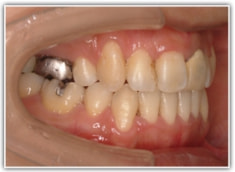

骨格的な下顎前突の傾向は強くはありませんが、歯牙の状態によって反対咬合が認められます。LowTongue(低位舌)もあります。

修復歯、補綴歯もあります。下顎8番が水平埋伏しています。

反対咬合の方はやはり下顎肢が細い傾向にあります。